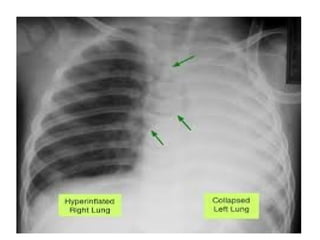

1)COMPLETE COLLAPSE

• Causes opaque hemithorax with

displacement of mediastinum to the

affected side with compensatory

hyperinflation of opposite lung often with

herniation across midline.

1)COMPLETE COLLAPSE • Causesopaque hemithorax with displacement of mediastinum to the affected side with compensatory hyperinflation of opposite lung often with herniation across midline. • Herniation mostly occurs in retrosternal space but may occur posterior to heart or under aortic arch